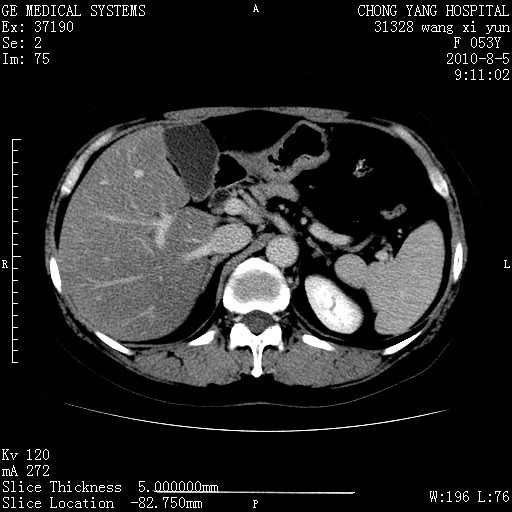

标题: CT28214:F41Y 血尿二十天,建议盆腔平扫加增强。

1)考虑肝左叶胆管细胞癌。2)脂肪肝。